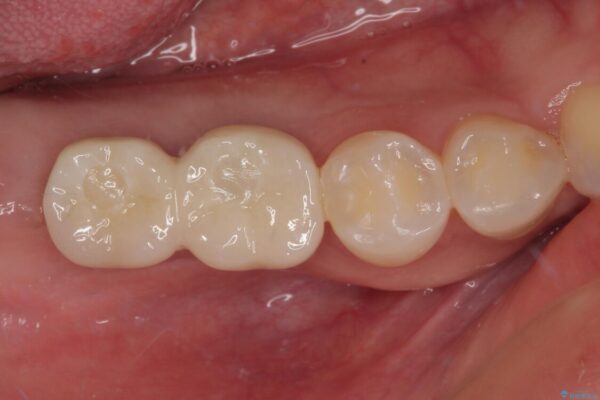

スペースが整った段階で、右下の第一大臼歯と第二大臼歯にインプラントを埋入。

その後、挺出していた右上第一大臼歯と第二大臼歯に装着されていた銀歯についても、審美性と適合性の向上を目的に、オールセラミッククラウンにやり替えました。

これにより、より自然で美しい見た目と、高い精度の咬合が得られています。

治療後

• 挺出歯を圧下してスペースを確保!目立たない部分矯正で下顎大臼歯にインプラント治療を実現 治療後画像